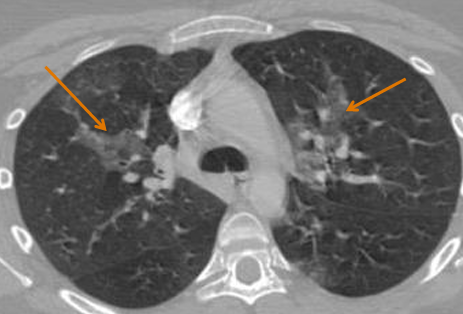

Clinique

- Dyspnée, Tachycardie

- Beaucoup de symptomes mimes → Peu de CT positifs (<5%)